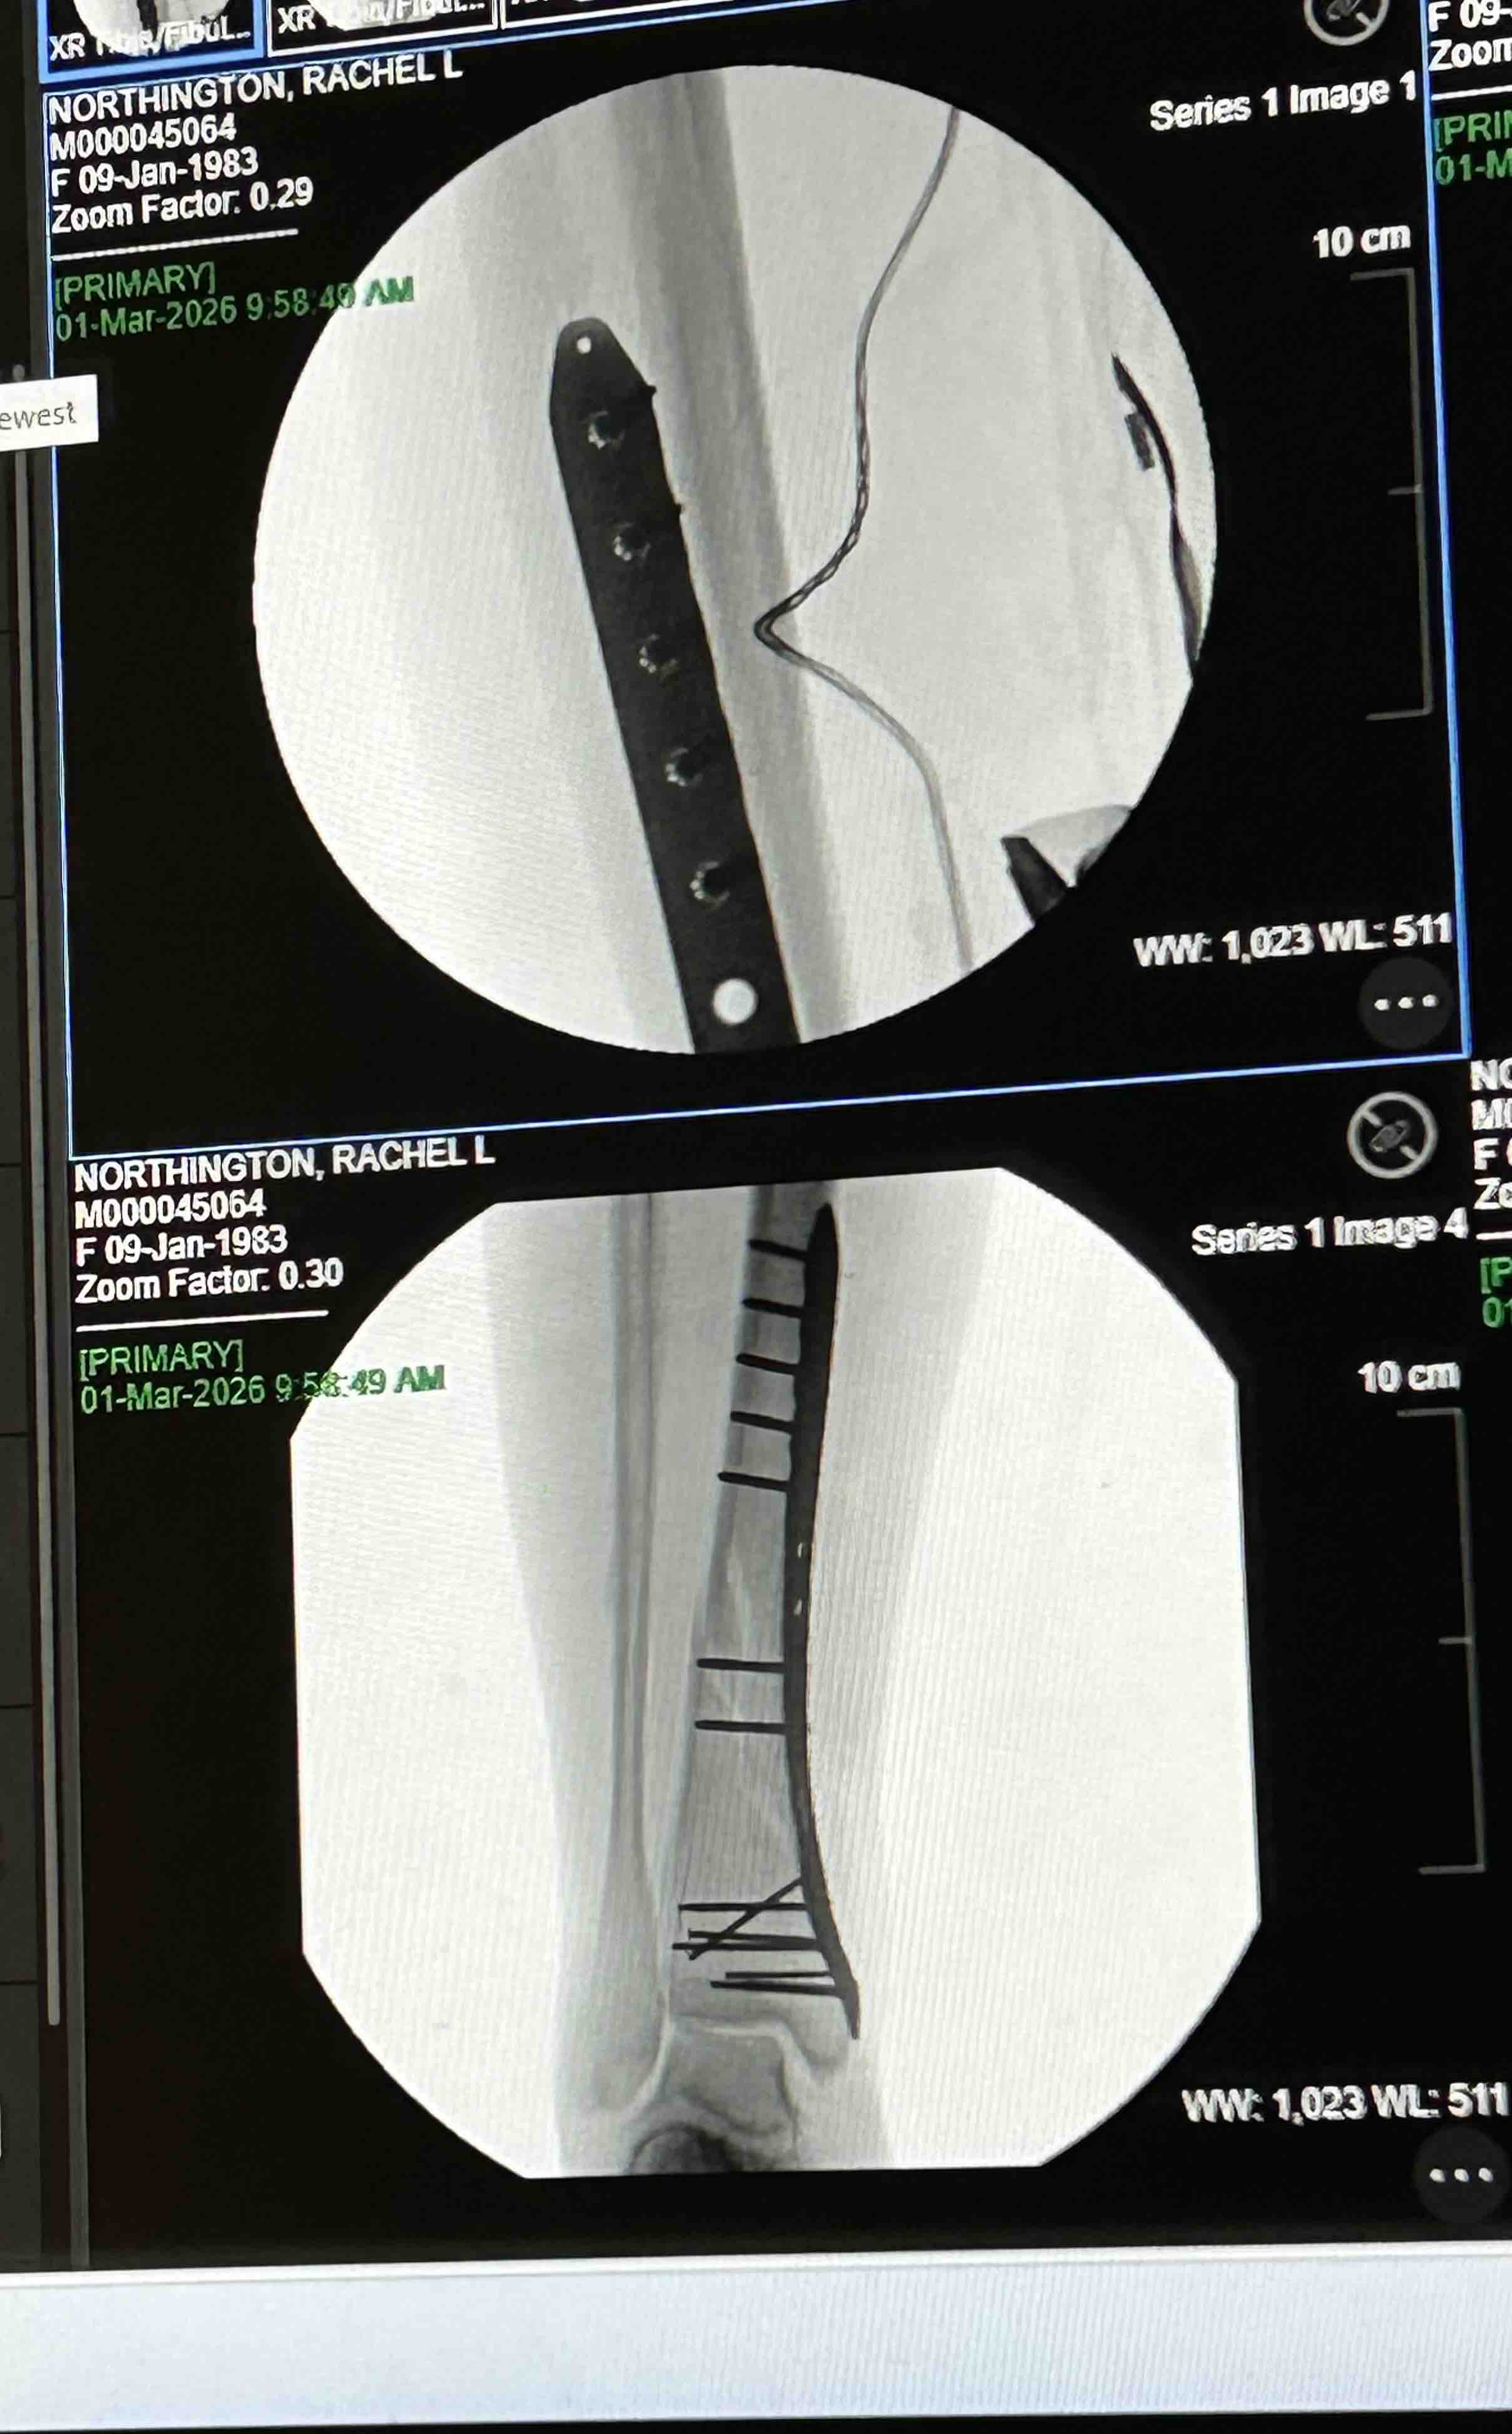

Hello my name is Rachel and I’m usually a pretty active and healthy girl. I was taken to the Murray Hospital February 15th and discharged on the 24th due to severe pancreatitis and pneumonia. I was home only a couple days and still felt very weak and tired. I attempted to go into my bathroom and somehow lost my footing and my whole body landed on my right leg and broke my right tibia and fibula (8.0 cm severely comminuted fracture of the proximal fibular shaft and 10.2 cm spiral fracture distal tibial shaft). 2 very bad fractures . It was the worst pain I’ve ever experienced! It took me 30 mins to crawl about 30 feet to my bed where my phone was to call 911 for help. The paramedics wouldn’t let me look at my leg and kept telling me to try to just lay down and relax, which was extremely hard to do. I was told my leg looked crooked and my foot was turned all the way to the side. With the help of the fire department, I was able to make it down my steps and to the ER. I had 2 doctors come in while in the ER and reset it the best they could until I could have surgery. Was supposed to be the next day but a special plate and screws had to be sent to the hospital so Sunday morning at 8am, an hour long surgery took almost 3. I now have a 9 inch place and 13 screws in my leg on one of the fractures. Depending on how the other fracture looks when I see my Ortho for follow up, I may need another surgery to put a plate on it as well. I am non weight bearing for 6-8 weeks and won’t be able to drive for no earlier than 6 months. Full recovery is a year or more. Since I am not currently working, I have applied and talked to many people about getting some sort of disability to help me keep my apartment but not getting a lot of good answers so far. I have even had my doctors send in letters stating my condition and how severe it is but it’s not getting anywhere. If anyone could find it in their heart to help me stay above water, I would greatly appreciate it!! Even a couple dollars goes a long way! All money will go to medical expenses including physical therapy, doctor appointments, medicine and the rental of medical equipment I need to get around. I didn’t want to have to make this but I’m in a rough place right now and could really use the help. Any help is appreciated. Thank you and God Bless!